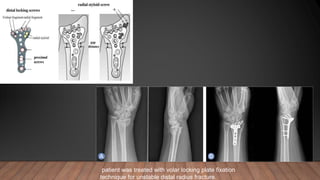

patient was treated with volar locking plate fixation

technique for unstable distal radius fracture.

patient was treatedwith volar locking plate fixation technique for unstable distal radius fracture.